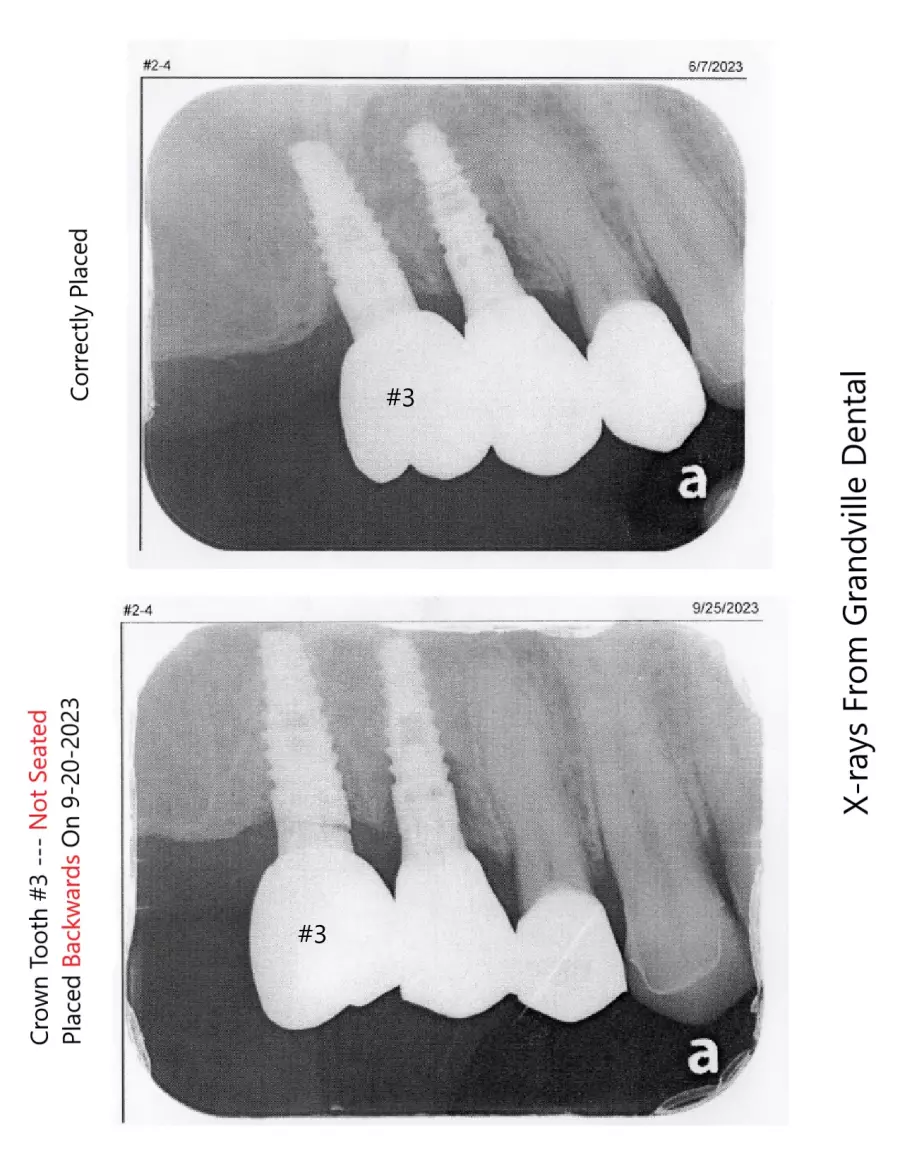

WMDDS please go look at photo #120 - This is a huge oversight error.

Dr. Rebecca Vanderbaan & Dr. Larissa Bishop The Past President Of The WMDDS Placed A Dental Crown Tooth #3 Backwards And Wrecked My Restoration. A Bridge became loose, A veneer chipped, A crown fell off, another crown became loose, 8 teeth are not touching each other and I have bone loss on several new implants likely caused from this.

How did a implant supported crown get placed 180 degrees backwards then get missed then several adjustments to the adjacent teeth were made on four different separate occasions until there was no bite on 8 teeth. Permanent adjustments were made to teeth #5, #6, #7, #26, #27 and #28 all based on a crown tooth number 3 being placed backwards and then let me go with a non-functioning bite.

The WMDDS should be looking hard at Photo #120 and look close at tooth #3 then compare it to the model the way the tooth was supposta be placed and you will see tooth #3 was placed 180 degrees backwards and not known for a whole year biting my tongue and cheek everyday over 300 times and sometimes to the point of bleeding and I told the dentist my tooth #3 is biting my tongue and check every single day but everyone ignored it and let me keep biting myself. Photo #120 is the photo that the dental association was weirdly missing. The WMDDS should go back and actually look at this case and see how the clinical exam was unfair, biased and no x-rays or bitechecks were even taken during there clinical exam.